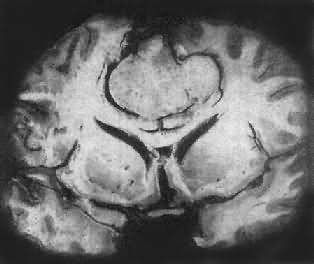

肉眼观,肿呈球形,分叶状或不规则形,质实或硬,边界清楚,周围脑组织受压成凹陷切迹(图16-27)。少数肿呈斑块状覆盖较广泛区域,甚至整个脑半球,称为斑块型脑膜。肿质地硬,切面灰白色,呈颗粒状、条索旋涡状,有的质地似砂砾样,乃由于有多量砂粒体存在。

图16-27 脑膜

于大脑两半球间有一近似球形肿,边界清楚,周围脑组织受压萎缩